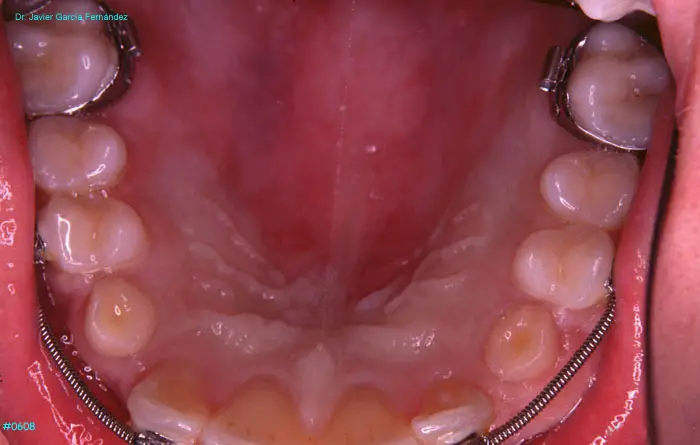

Atlas of Surgical Techniques in Periodontics. Chapter II. Atlas de Técnicas Quirúrgicas en Periodoncia